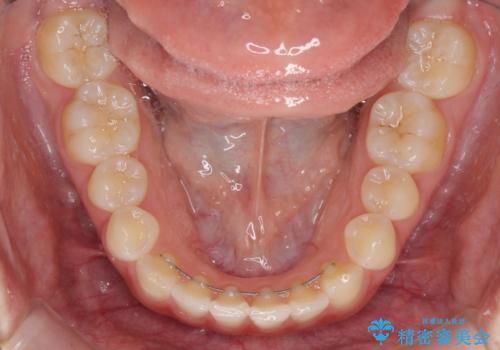

- 1年後に海外に転居するため、気になる前歯を矯正治療で整えたいとのことで来院された患者様です。

下顎は叢生が強かったため、奥歯までワイヤーを装着し、上顎は前歯の一部のみ気になっていたので、その部分にだけワイヤー装置を装着することとしました。

部分矯正は、適応となる症例が限定されます。

こちらの患者様は部分矯正が可能な、非常に珍しい方でしたが、部分矯正を希望される患者様の大半は、全顎矯正が必要となります。